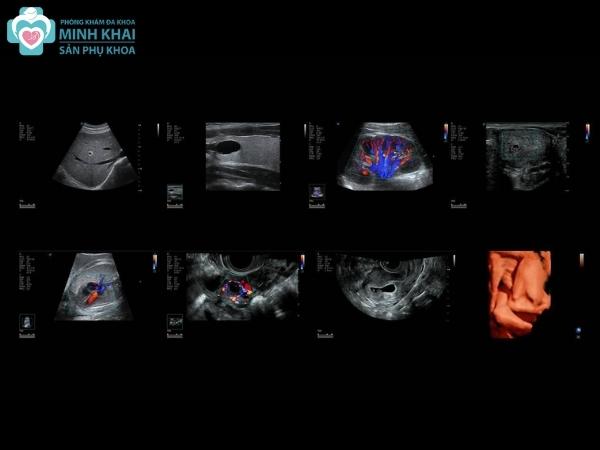

Ngay từ những ngày đầu tiên của thai kỳ, mẹ bầu sẽ được bác sĩ khuyến khích sử dụng kỹ thuật siêu âm thai 2D. Nó sẽ tái hiện lại được cấu trúc của bào thai qua bức hình đen trắng theo nguyên lý chỗ có mô cơ thể càng đặc thì màu xám trắng càng đậm. Từ đó, người mẹ có thể biết được số lượng bào thai, khảo sát vị trí đậu thai trong hay ngoài tử cung, các chỉ số sinh trắc học (tuần tuổi, kích thước,...) của thai nhi.

Kết quả siêu âm 2D cũng báo hiệu được những bất thường trong thai kỳ của người mẹ liên quan đến buồng trứng, tử cung. Ngoài ra phương pháp siêu âm này còn cho phép đánh giá được toàn diện sự hình thành và phát triển của thai nhi qua theo dõi độ lớn vòng đầu, kích thước xương đùi cũng như phát hiện sớm những dị tật bẩm sinh như bệnh down, hở hàm ếch, sứt môi, tay chân dính liền,...

Siêu âm 2D phản ánh cấu tạo từng bộ phận của thai nhi qua hình ảnh các mặt cắt 2 chiều trong cùng một thời điểm.

Siêu âm 3D thể hiện hình thái của thai nhi qua hình ảnh không gian 3 chiều ngay trong thời gian thực.

Siêu âm 4D thể hiện được cấu trúc bên ngoài và nội soi cấu tạo bên trong của thai nhi qua hình ảnh không gian 3 chiều trong cùng một chiều thời gian. Vậy nên nó có thể tái hiện lại hoạt động của thai nhi qua ảnh động hoặc video ngắn

Siêu âm 5D chính là sự phát triển về công nghệ của siêu âm 4D khi được kết hợp thêm 1 chiều chẩn đoán tự động.

Siêu âm 2D tái tạo lại hình ảnh tổng quát về cấu tạo và hình thái của thai nhi. Không chỉ vậy nó còn thu lại được chi tiết các bộ phận của bé cũng như xác định được tư thế, vị trí nằm của thai nhi ở buồng tử cung người mẹ. Do đó siêu âm 2D sẽ tạo điều kiện tốt để bác sĩ phân tích hình ảnh và phát hiện bất thường, dị dạng khuyết chi, chi dính liền, hở môi hàm ếch,...

Siêu âm 3D, 4D, 5D cũng giúp bạn theo dõi được bức ảnh tổng thể và chi tiết các cơ quan của thai nhi. Tuy nhiên chất lượng hình ảnh của chúng sẽ rõ ràng và sắc nét hơn siêu âm 2D gấp nhiều lần. Thậm chí siêu âm 4D, 5D còn có thể phản ánh cử động của thai nhi rõ ràng, chân thật qua các bức ảnh động.